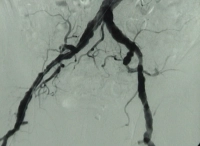

DAOP perna direita grau IV de Fontaine, perna esquerda grau III com:

- Arteriosclerose de alto grau da aorta terminal e de ambas as artérias ilíacas

- Oclusão estendida de ambas as artérias femorais superficiais

- Oclusão parcial das artérias infrapoplíteas em ambas as pernas

DSA pré-operatória: